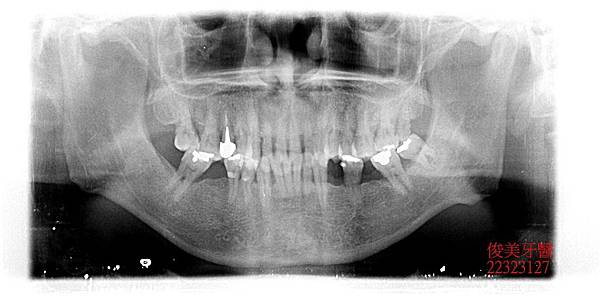

患者為男性,年約46歲,於門診時表示,牙齒有牙周病,想要將牙齒修復,經資料搜集後, 找到我們診所,希望可以做全口性整修;經醫師檢查後發現:患者因有多顆缺牙未做,日積 月累,牙齒造成傾倒,咬合跑掉導致前牙受力過重,牙周狀況不佳,因此為患者設計療程並 詳細說明,患者接受了。

前牙受力重,牙齒已飆出來。

上、下顎落差大,造成深咬。